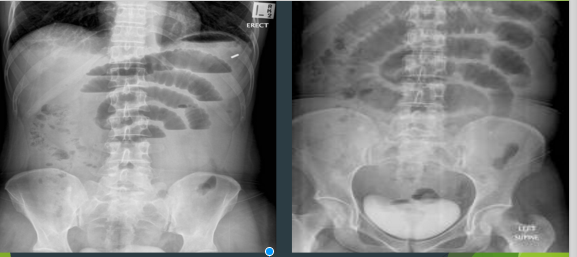

SMALL BOWEL OBSTRUCTION

TWO PATIENTS WITH

What are these two xrays showing?

What symptoms come with this pathology? 3